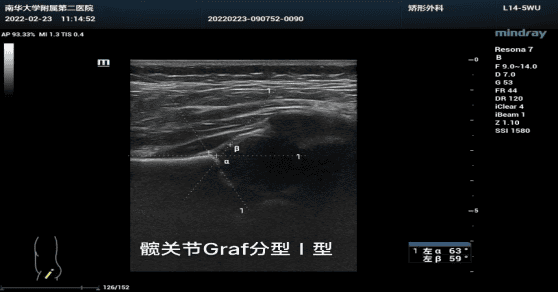

可评估髋关节形态与位置是否正常,其临床检测技术具操作简单,有固定评估标准,无放射性检测,可多次重复检测的特点,因此作为较大范围婴幼儿DDH筛查首选检测技术。